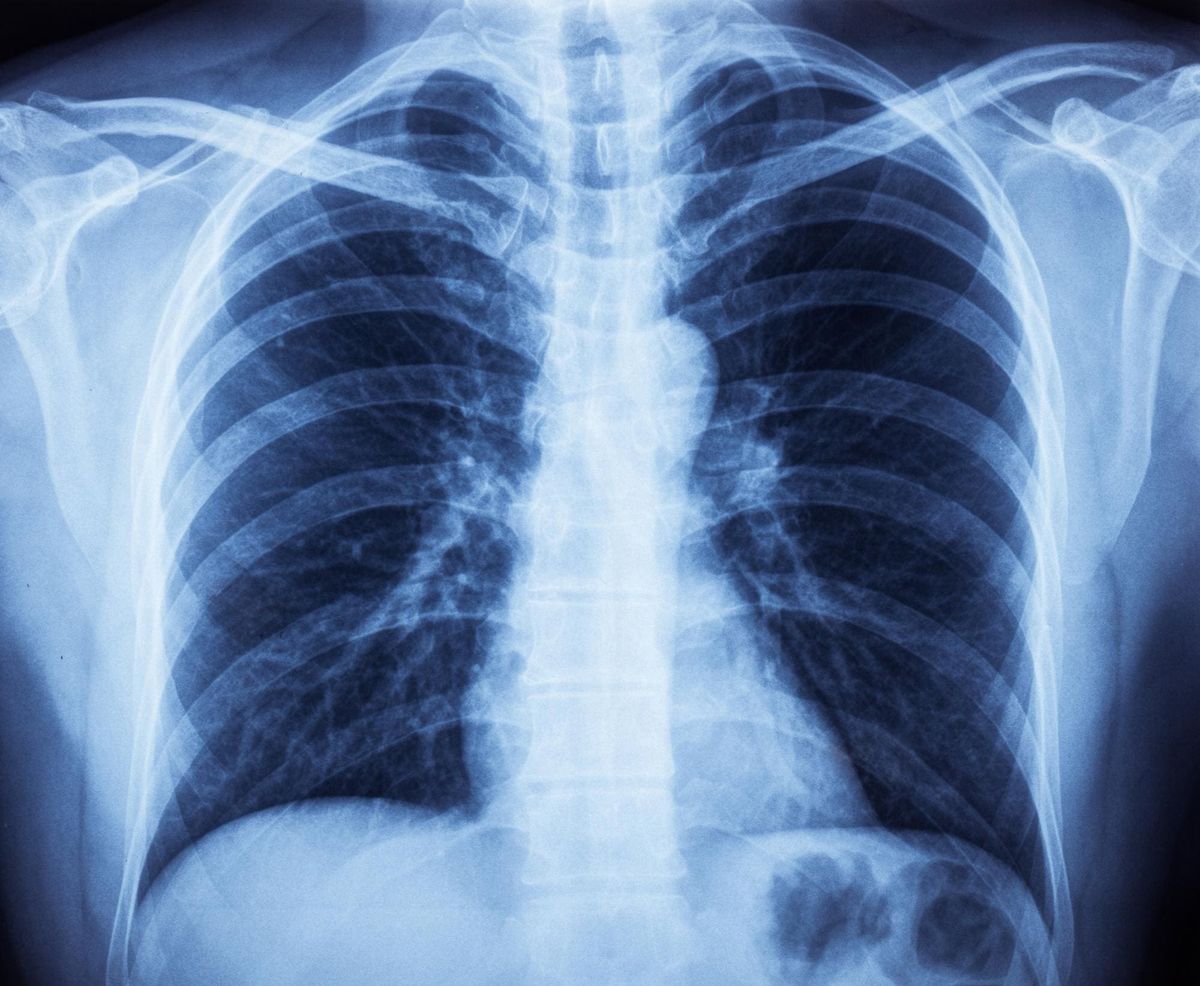

Диагностика

Боль в ребрах — это всего лишь один из симптомов патологии. Для того чтобы избавиться от нее, нужно обратиться за помощью к врачу травматологу, неврологу или терапевту. Дальше нужно будет пройти обследование и устранить само заболевание. Вам могут назначить один или несколько из нижеприведенных методов диагностики:

Основные методы диагностики боли в ребрах

Методика диагностики Время

ЭКГ 30 минут

Общий анализ крови 10 минут

Эхокардиография 30 минут

Pентген грудной клетки 10 минут

Стоимость обследования находится в пределах от 500 до 4000 рублей. После обследования назначается курс терапии.